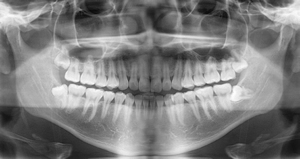

デジタルレントゲン

デジタルレントゲンは何より「被曝量が低い」事が最もメリットであり、それでいて高画質な画像で記録・診断することが可能です。

それにより、患者さん皆様の歯列形状をより詳しく、それぞれ皆様にあわせた診断を目指しています。